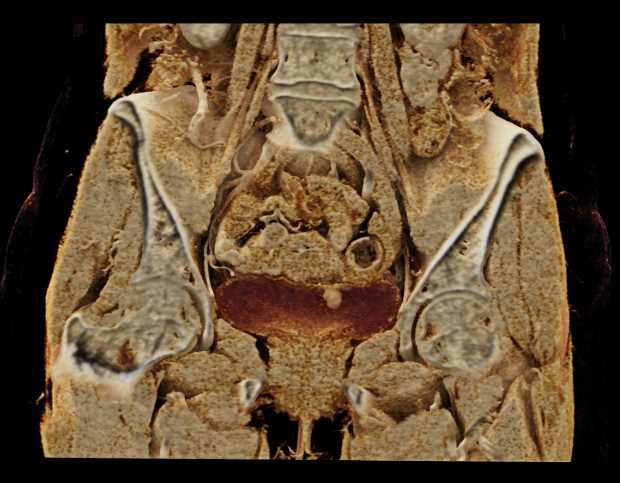

Urachal Carcinoma of the Bladder